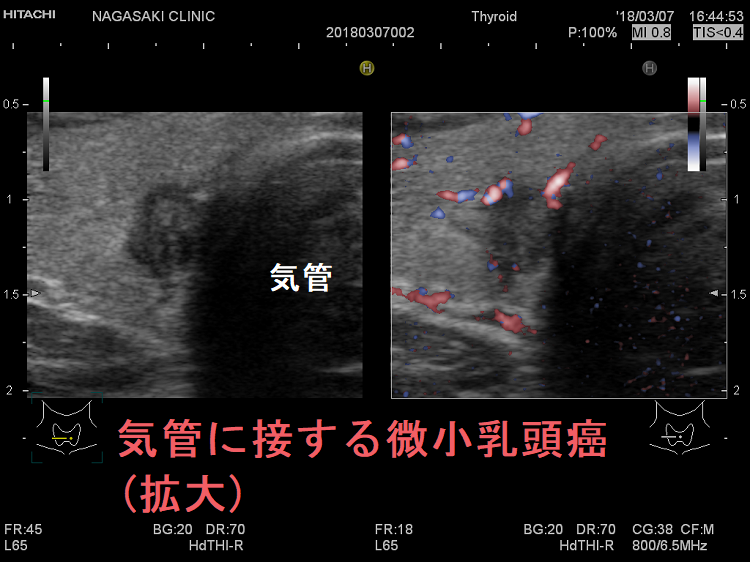

- 気管に浸潤している可能性がある[気管との間に被膜なく、鈍角で(アワビ状に)気管に接している]・甲状腺背面に鈍角で(アワビ状に)反回神経に接する7mm以上の甲状腺微小乳頭癌は、気道内への出血・反回神経麻痺の危険から、甲状腺を半分切除~全部摘出せねばなりません。(Thyroid. 2016 Jan 1; 26(1): 144–149.)(World J Surg 2016;40:523–528.)(下記)

隈病院でも、鈍角で(アワビ状に)気管に接する甲状腺微小乳頭癌(図のA)は、手術適応にしています(Thyroid. 2021 Feb;31(2):183-192.)

上のエコー画像は長崎甲状腺クリニック(大阪)の自験例です。気管に鈍角で(アワビ状に)接していませんが、拡大画像を見れば分かるように、明らかに甲状腺を包む被膜が消失し、気管に浸潤している様に見えます。